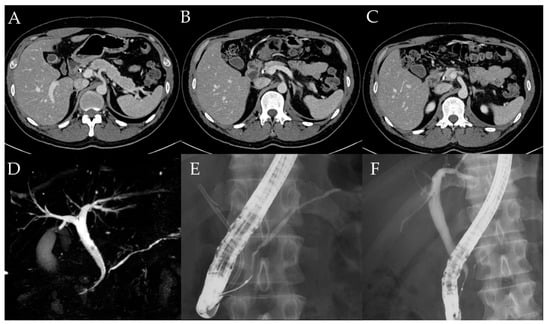

3.4. Case Report (Case 10)